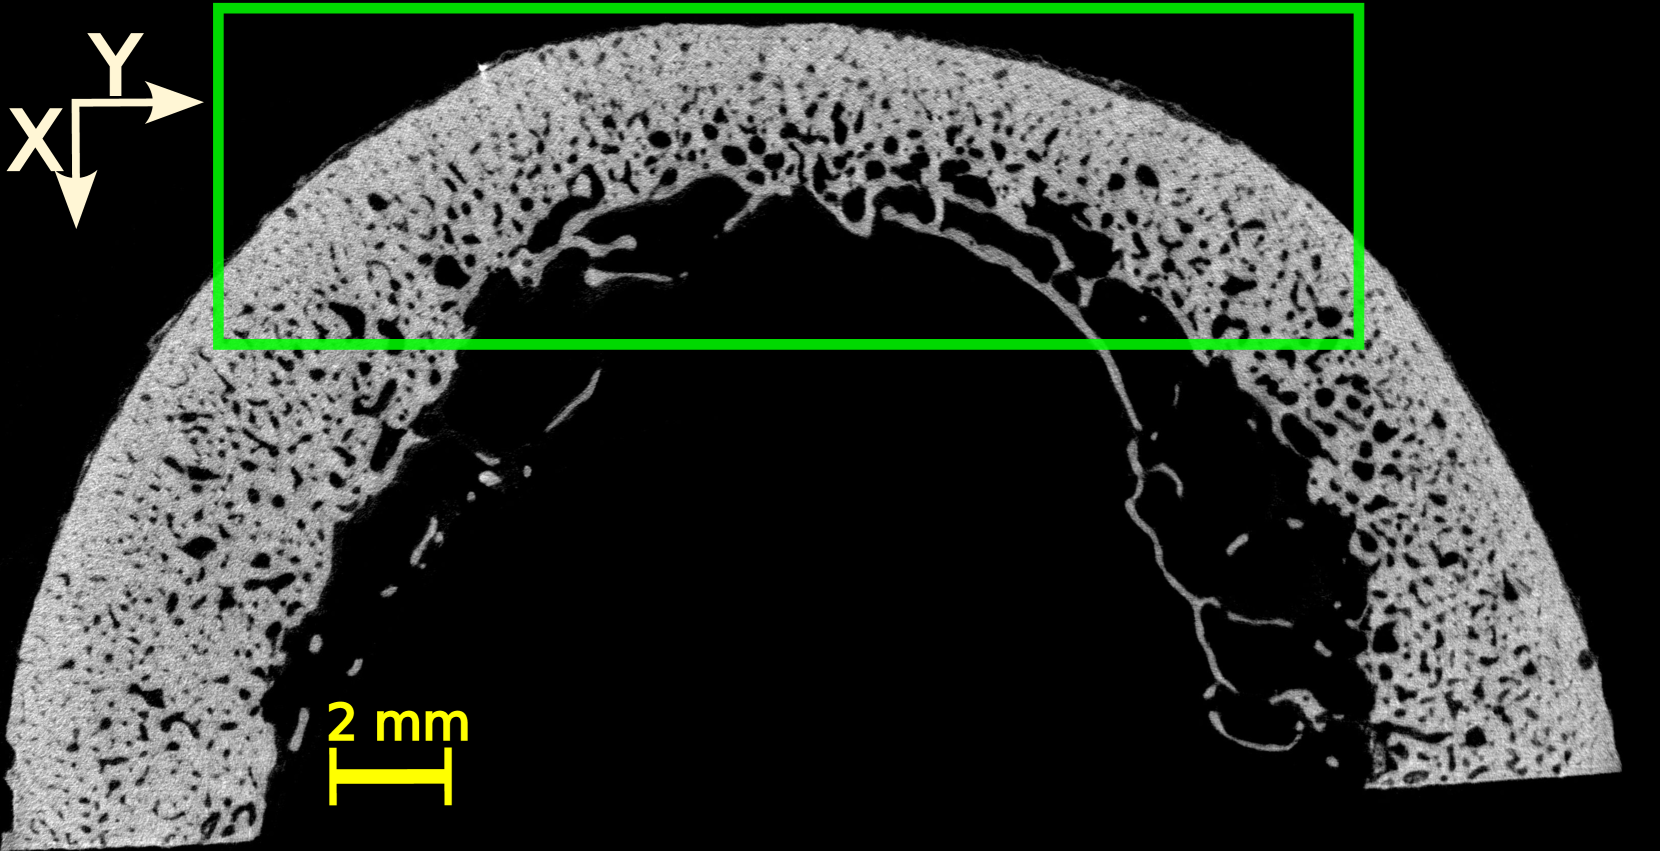

Four volumes of interest (VOI) were defined within the three-dimensional (3D) HR-µCT image of each sample. The thickness (direction of the bone axis) and width of the VOIs were 15 and 20 mm, respectively. The height of the VOIs varied between 8 and 10 mm, depending on the cortical thickness and diameter of each sample. Figure LABEL:method:example_xray_slice shows a two-dimensional (2D) slice in the transverse plane extracted from each VOI for all the samples. The VOI’s dimensions approximately correspond to the thickness (probe elevation direction), lateral dimension (probe aperture) and depth of the US image.

The initial step was to apply a Gaussian filter (round kernel of radius 2 or 3, depending on the sample) to remove acquisition noise. Then, the VOI were binarized using 3D Otsu method [31]. Given that this study focuses on the cortical bone tissue, we removed, in the endosteal region, the bone remnants resulting from a trabecularization [5] of the cortex (samples 4 and 5, see Figure LABEL:method:example_xray_slice and Figure S1 in supplementary materials). To do this, we used kernel filtering (either Kuwahara or Uniform kernels with a radius of 2) and morphological operations to close all pores below a specific threshold diameters, thereby generating a mask that excluded trabecular regions. The specific choice of kernel and parameters varied across samples to accommodate the high morphological variability among the samples (Figure LABEL:method:example_xray_slice).

The 20 VOIs (4 VOIs in each of the 5 samples) showed a great diversity in terms of cortical thickness, porosity, and distribution of pores (Figure LABEL:method:example_xray_slice). Cortical thickness estimated from micro-CT images ranged from 2.5 to 6.3 mm (Table LABEL:table_chap_4:pore_stat_samples_combined). The microstructure parameters are summarized in Table LABEL:table_chap_4:pore_stat_samples_combined. Samples 1 and 2 had the lowest porosity (5–6.4 % and 5.3–6.7 %, respectively) and no large pores (Lg.Po.Dm 175 m). Sample 3 showed moderate porosity (7–12.3 %) with moderately large pores (Lg.Po.Dm in the range 224–228 m). Samples 4 and 5 presented the highest porosity (12.2–16 % and 16.4–16.6 %, respectively) with 10% of the pores with diameter above 300 m. Sample 4 displayed the largest pores (Lg.Po.Dm in the ranged 334–423 m), which can be clearly seen in Figure LABEL:method:example_xray_slice. Porosity values and the porosity gradient from the periosteal to the endosteal surface seen in some samples are consistent with the literature data for elderly donors [27].